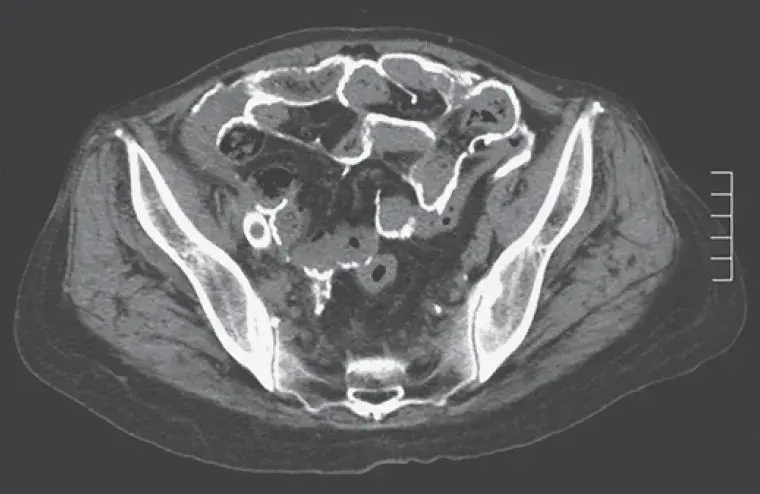

- Isquemia de circulação mesentérica (cólon, intestino delgado e estômago